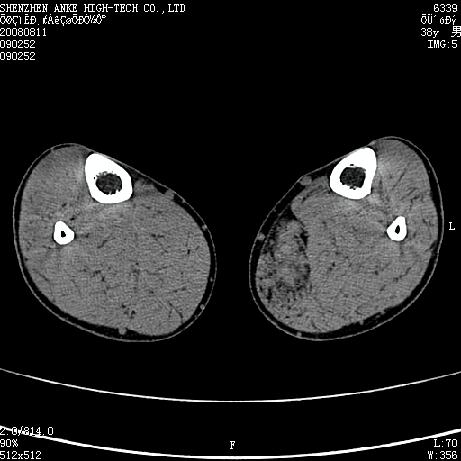

标题: CT15117:M38Y,小腿平扫 [打印本页]

标题: CT15117:M38Y,小腿平扫

患者,男,38岁,右小腿疼痛性包块1月,查体:右小腿可扪及约5x4cm大小包块,压痛.

左小腿内侧软组织病变,性质待定(血管瘤?);建议行mri检查。